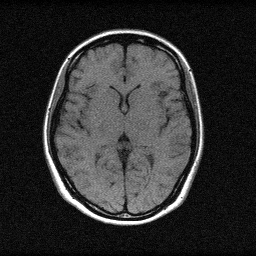

Method: CPU_baseline | Mismatch: nominal (nominal=True, perturbed=False)

Ground Truth

Measurement (perturbed)

Reconstruction